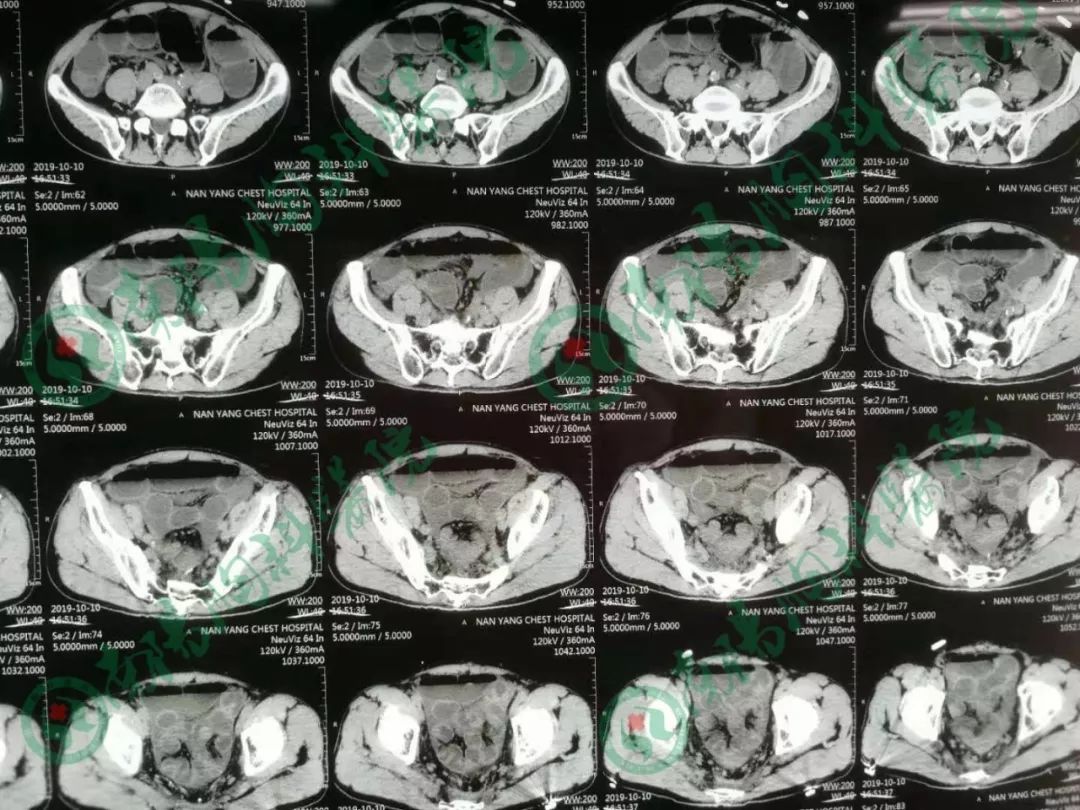

患者经过立位DR和CT检查均提示肠管高度扩张,多发阶梯状液平,病情非常棘手。

告知急诊手术,术中探查见小肠高度扩张,末段回肠扭转粘连于盆底骶前,放射性肠炎改变,呈冻结状,部分肠管受压坏死,行末段冻结扭转回肠切除术,小肠造瘘术,术后病人生命体征平稳,安返ICU。